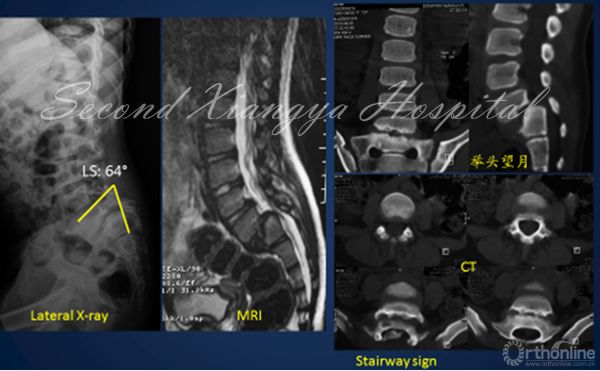

1. 骶骨形态重度不良

对重度骶骨发育不良者,先天遗传是主要原因。2015年,罗卓荆团队通过两个家系[6],鉴定了2个新型错义突变,功能研究显示软骨发育过程中,磷酸化摄入障碍是其发病主要的分子机制。遗传因素造成的骶骨穹窿形态不良,通常较为严重,并会造成L5椎体梯形变,导致滑脱进展,并使得外科治疗此类畸形较为困难。

2. 骶骨形态不规则

骶骨形态不规则,通常是由于力学因素造成的。2012年,Sevrain[7]根据PI值将滑脱分为低PI组和高PI组,生物力学测试结果表明,低PI组人体重心位于骶骨中后区,而高PI组重心则分布在骶骨前方。从而更容易造成骶骨形态发生轻度或中度形态变化,L5椎体出现相应梯形变,从而亦会造成滑脱进展。